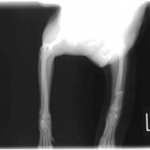

症例:交通事故による椎体脱臼

柴犬:9歳、避妊雌

交通事故直後、胸腰部に激しい疼痛、両後肢に完全麻痺を認め、シェフシェリントン徴候を呈していました。レントゲン検査において、第11-12胸椎間の脱臼が認められました。

脊髄の減圧、脊柱管の再構築・安定化を目的に、片側椎弓切除術およびMatrixMANDIBLE Plateによる椎体固定を実施しました。

隣接椎体を架橋するようにプレートを設置しました。

術後レントゲン写真